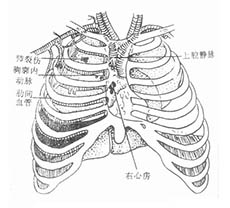

冠状动脉粥样硬化性心脏病

疾病介绍:冠状动脉粥样硬化性心脏病是冠状动脉血管发生动脉粥样硬化病变而引起血管腔狭窄或阻塞,造成心肌缺血、缺氧或坏死而导致的心脏病,常常被称为“冠心病…【详细】

心脏瓣膜病及其他疾病

疾病介绍:心脏瓣膜病及其他疾病心脏瓣膜病就是指二尖瓣、三尖瓣、主动脉瓣和肺动脉瓣的瓣膜因风湿热、黏液变性、退行性改变、先天性畸形、缺血性坏死、感染或创…【详细】

心脏瓣膜病及其他疾病

疾病介绍:心脏瓣膜病及其他疾病心脏瓣膜病就是指二尖瓣、三尖瓣、主动脉瓣和肺动脉瓣的瓣膜因风湿热、黏液变性、退行性改变、先天性畸形、缺血性坏死、感染或创…【详细】

新生儿持续肺动脉高压(PPHN)

疾病介绍:新生儿持续肺动脉高压是由多种病因引起的新生儿出生后肺循环压力和阻力持续增高,而发生心内水平(通过卵圆孔)和(或)动脉导管水平的右向左或双向分流,…【详细】